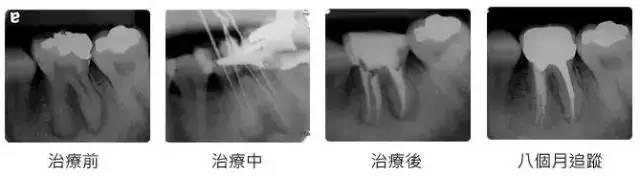

3、定期口腔检查,每半年或者一年检查根管后牙齿的情况,根管后根尖的状况。